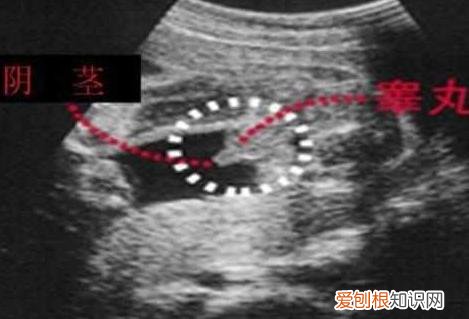

【四维照片一看就是男孩 b超有两点基本是男孩】男宝宝的B超图:男宝宝的B超图上其实是能看到小鸡鸡的,图片的红圈处就是,这张图片上的小鸡鸡比较清晰,医生取的那个角度就是宝宝屁股正下方,看的很清楚 。凸出的东西 是他的标记: 看到圆圆的是睾丸,如果看到圆圆的如小肠的东西就是全部鸡鸡 。